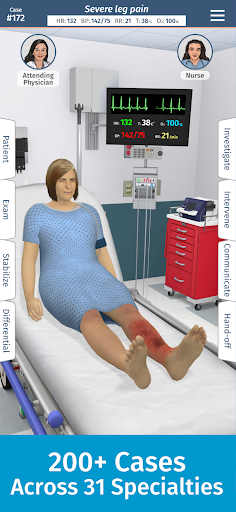

• 200+ thư viện trường hợp được biên soạn và đánh giá bởi các bác sĩ lâm sàng chuyên gia

• Hơn 30 chuyên khoa chẩn đoán, bao gồm Y học cấp cứu, Sản phụ khoa và Nhi khoa

Mỗi trường hợp đều là một thách thức mới trong Full Code: từ chẩn đoán thông thường đến các bệnh hiếm gặp. Bạn không chỉ giới hạn ở bệnh viện—Full Code đã mở rộng sang nội dung trước khi nhập viện và EMS. Ra khỏi khoa cấp cứu và vào xe cứu thương để ứng phó với mọi tình huống mới!